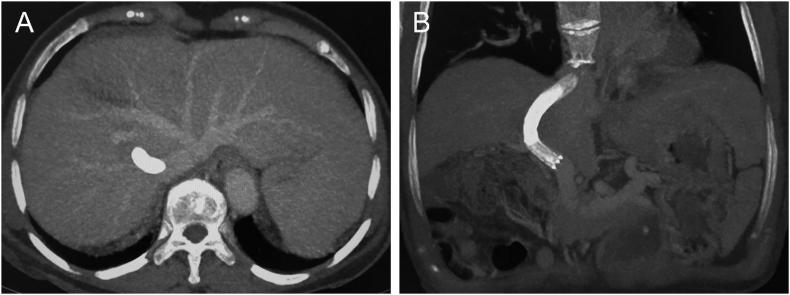

We report the case of a female patient with a 20-year history of hepatitis B virus infection who presented with repeated bleeding of hemorrhoids caused by severe portal hypertension with ectopic varices that is connection between the superior mesenteric vein and rectal venous plexus. Laboratory results revealed a hemoglobin level of 74 g/L. Finally, the patient was successfully treated with transjugular intrahepatic portosystemic shunt (TIPSS) placement without variceal embolization after a multidisciplinary comprehensive opinion. In the two-month follow-up period, the patient had failed to develop hepatic encephalopathy or hematochezia, and computed tomography venography (CTV) indicated that the stent was unobstructed and ascites disappeared.

TIPSS placement is effective for the case, and we hope this case can help improve clinicians' awareness of hemorrhoidal bleeding with severe portal hypertension. Portal hypertension should also be considered during the diagnosis and treatment, as opposed to hemorrhoidal bleeding alone. Moreover, abdominal CTV is recommended as an effective imaging examination method to determine the stent status after operation.

我们报告了一例有20年乙型肝炎病毒感染史的女性患者,该患者因严重门静脉高压伴异位静脉曲张(即肠系膜上静脉与直肠静脉丛之间的连接)导致反复痔疮出血。实验室检查结果显示血红蛋白水平为74 g/L。最后,经多学科综合评估后,患者成功接受了经颈静脉肝内门体分流术(TIPSS)植入,未进行曲张静脉栓塞。在两个月的随访期内,患者未发生肝性脑病或便血,计算机断层扫描静脉造影(CTV)显示支架通畅,腹水消失。

TIPSS植入对该病例有效,我们希望该病例能提高临床医生对严重门静脉高压症所致痔疮出血的认识。在诊断和治疗过程中,除了单独考虑痔疮出血外,还应考虑门静脉高压症。此外,建议采用腹部CTV作为确定术后支架状态的有效影像学检查方法。